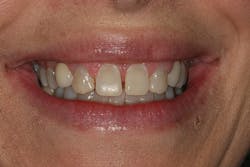

A 32-year-old white female presented for a cosmetic consultation. The patient reported that during her teenage years she had received orthodontic treatment to move her permanent maxillary canines mesially into the spaces that should have been occupied by her congenitally missing lateral incisors. She stated that her dentist, orthodontist, and oral surgeon had decided to place endosseous implants in the canine spaces due to the greater availability of bone in comparison to the bone available in the lateral positions (figure 1). As she grew older, she had become increasingly dissatisfied with the appearance of her smile and was seeking a more updated and esthetic solution (figure 2).

Figure 1